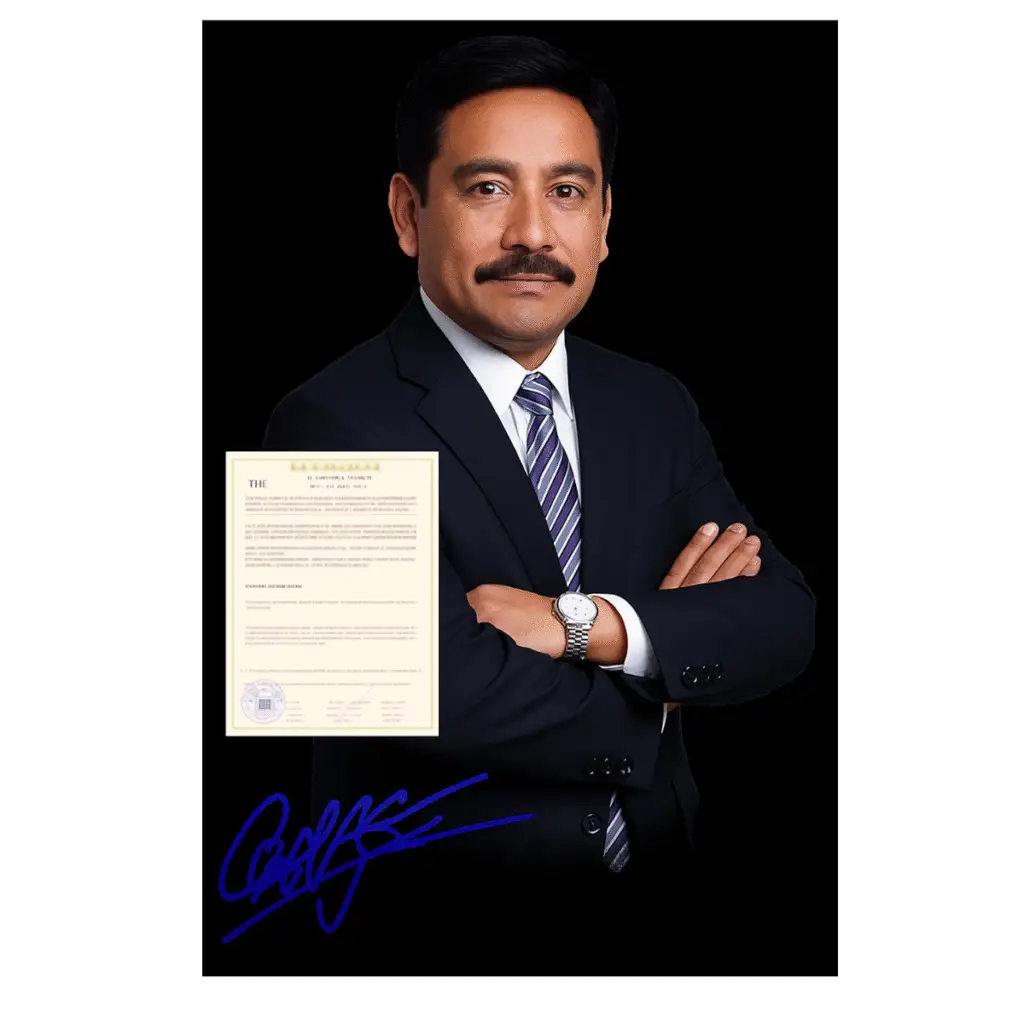

OPINIÓN DE UN OFTALMÓLOGO

¡Hola a todos! Mucho gusto, mi nombre es Dr. José Manuel Herrera. Llevo 13 años trabajando como especialista en oftalmología. En los últimos años, el número de personas que sufren pérdida de visión ha aumentado hasta 18 veces. Muchos de ellos hacen un uso constante de dispositivos electrónicos y gadgets, probablemente debido a la era de la digitalización. Muchos pacientes llegan a mi consultorio pensando que la única solución es aumentar la graduación de sus lentes o la cirugía. ¡Pero se equivocan! Las gafas solo ofrecen una ayuda temporal. Vizinex es lo que normalmente recomiendo a mis pacientes. En el 99% de los casos, las personas pueden ver con claridad y nitidez tras solo un ciclo de tratamiento. Sí, este suplemento es muy efectivo si se toma de forma regular y según las necesidades. Es seguro de consumir porque todos sus componentes son de origen natural. Gracias a su fórmula perfectamente equilibrada, estoy convencido de que se trata de una creación única que puede mejorar significativamente su visión. ¡Pruébelo, y quedará satisfecho con los resultados!